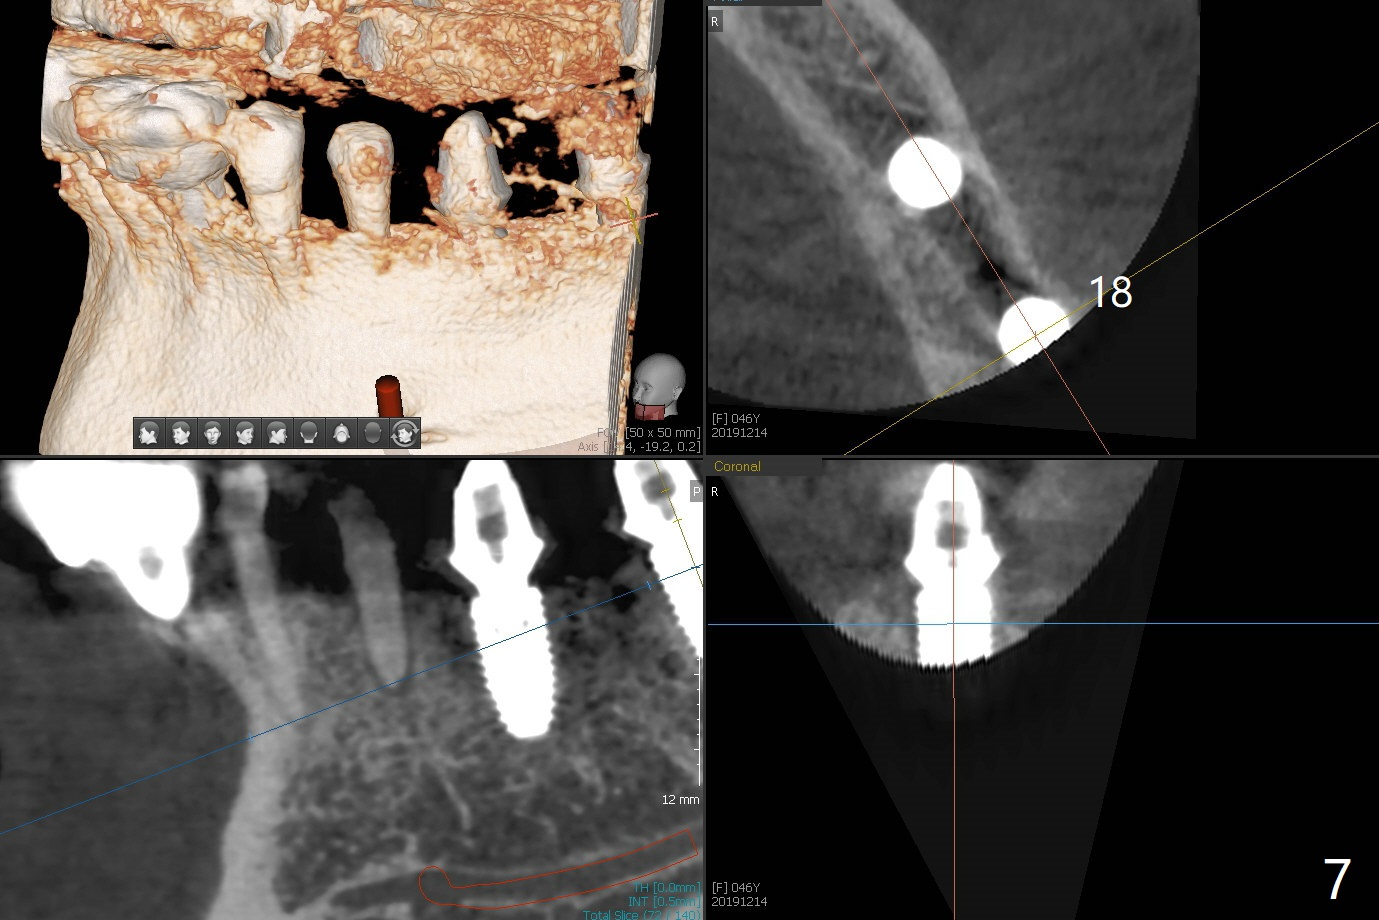

Re-analysis of preop CT reveals extensive bone loss around #18 (Fig.1 (lingual view)). Blood is withdrawn for sticky bone. After implant placement (Fig.2), sticky bone is placed at #18 (Fig.3 red dashed line (yellow: superior border of the Inferior Alveolar Canal)). PRF membrane and an immediate provisional FPD (#18-20) further keep the bone graft in place for healing. Four months postop, the patient reports difficulty in mastication on the left and requests extraction of the tooth #20 for implant (Fig.4). The implant will be placed lingually, while socket shield will be performed buccally (Fig.5 S) to keep bone graft in place. The implant at #19 is equicrestal (Fig.6); the one at #18 is apparently supracrestal buccally (Fig.7). Since there is a lot of scattering from nearby crowns, the implant at #20 will be placed free hand. To overcome the thick dense lingual plate (Fig.8 L), osteotomy is initiated (Fig.9 red line) in the middle of the lingual wall of the extraction socket (black area) on the top of the socket shield (S). After the last drill (3.5x11.5 mm, Fig.10 pink) and before 4x11.5 mm implant, use Lindamann bur to remove the coronal portion of the lingual plate (Fig.11 red line) to prevent implant buccal deviation.